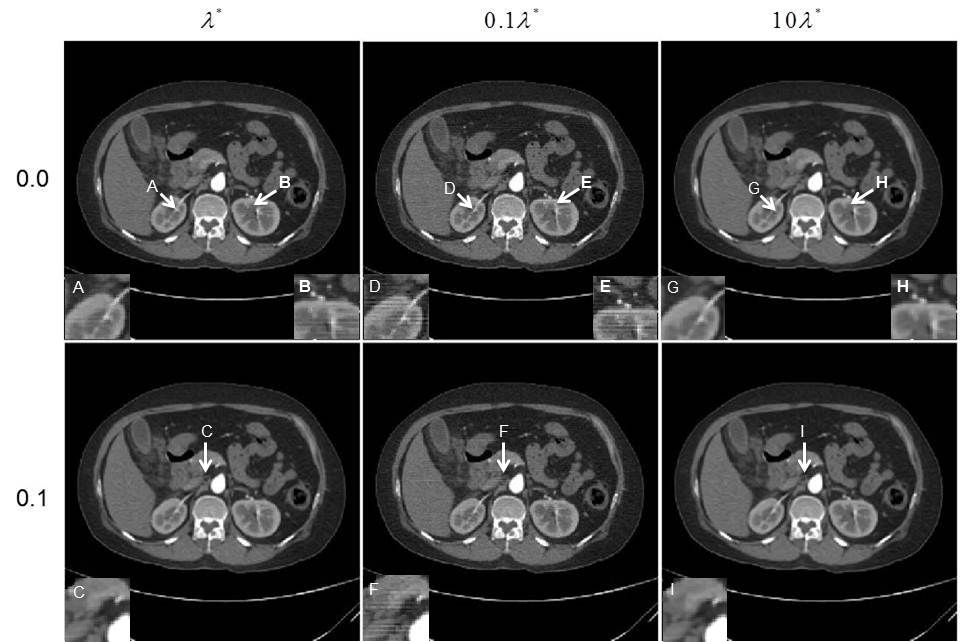

图1. 正则化参数选取模型有效性和准确性验证。第一列是利用选取模型得到正则化参数的重建结果,第二列和第三列分别取该参数的0.1倍和10倍。第一、二行分别为无噪声投影数据以及加入0.1%高斯噪声的投影数据的重建结果。结果表明参数选取过小(0.1倍,第二列结果)会使重建图像产生条形伪影和较高的噪声水平,参数选取过大(10倍,第三列结果)会使重建图像信噪比和空间分辨率降低。